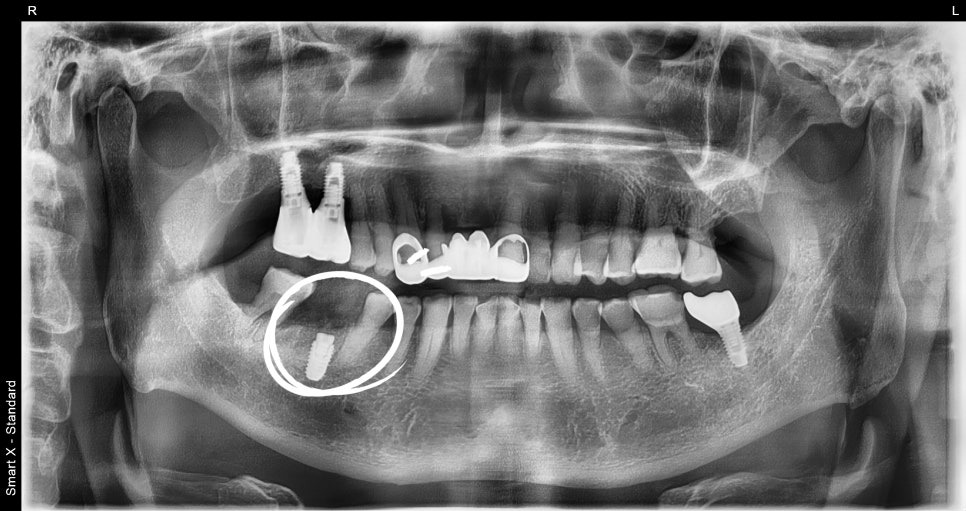

The Implant Placement Process

After molar extraction, implant placement is performed.

At this stage, what matters most is the condition of the bone.

Because the molar area often lacks sufficient bone, bone grafting is often performed together.

In this patient’s case as well,

guided bone regeneration and allogeneic bone grafting were performed together.

Implant price varies depending on whether such bone grafting is needed.